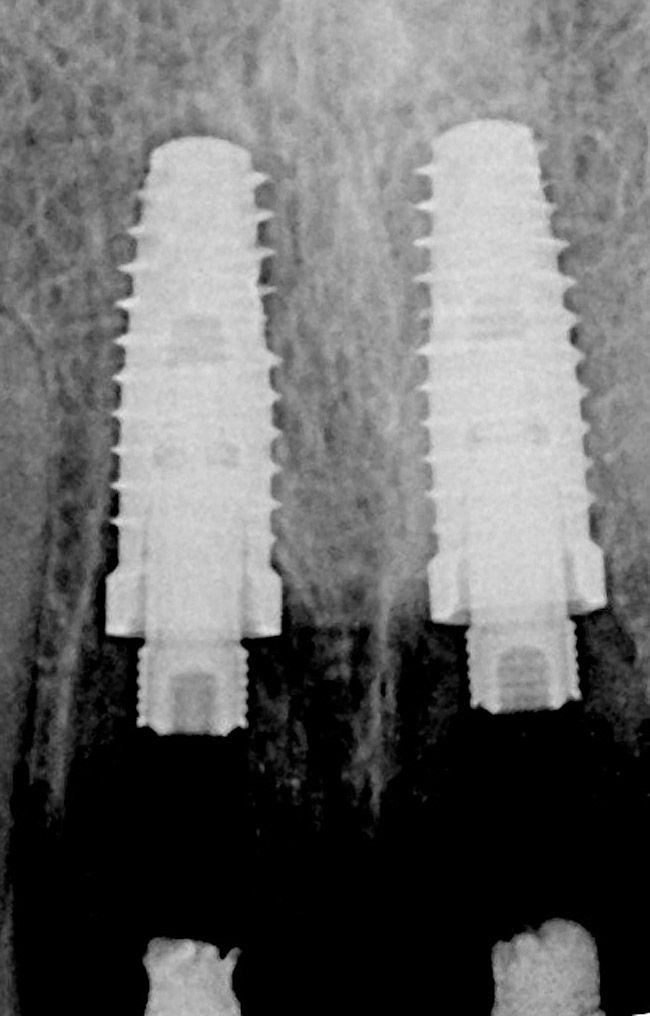

Figure 3  Periapical radiograph of implants in the Nos. 8 and 9 sites 3 years after placement. A bony peak was still present between the implants due to successful guided bone regeneration and favorable fixture spacing.

Figure 3

Figure 10   Periapical radiograph at the time of provisionalization. Note the wide peak of bone between implants Nos. 8 and 9.

Figure 10